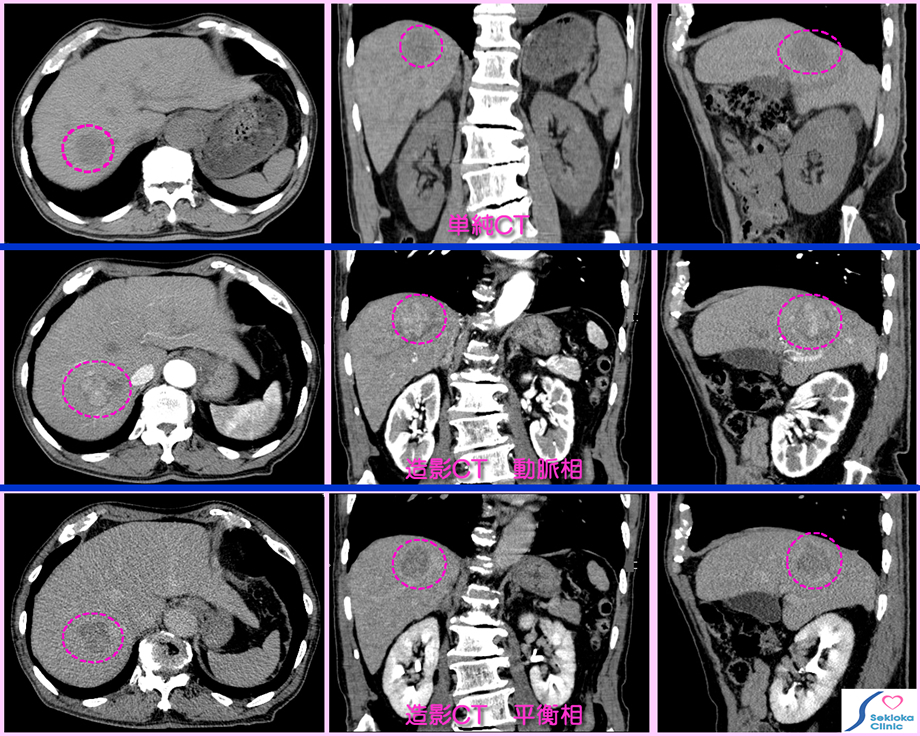

| 診断 | 原発性肝がんは肝硬変や慢性肝炎(C型肝炎,B型肝炎)などで定期的に超音波エコー検査やCT検査をしていて見つかることが多い。血液生化学検査ではα-フェトプロテイン、PIVKA-IIなどの上昇。転移性肝ガンや他の腫瘍との鑑別のため造影剤を用いてCT画像を造影剤注入後の時間経過で3-4相(下段は3相の撮影例)撮影し、腫瘍(癌)部及び周囲の血管(動脈・門脈)などの血液潅流状態、形状から癌の種類を鑑別推定します。 |